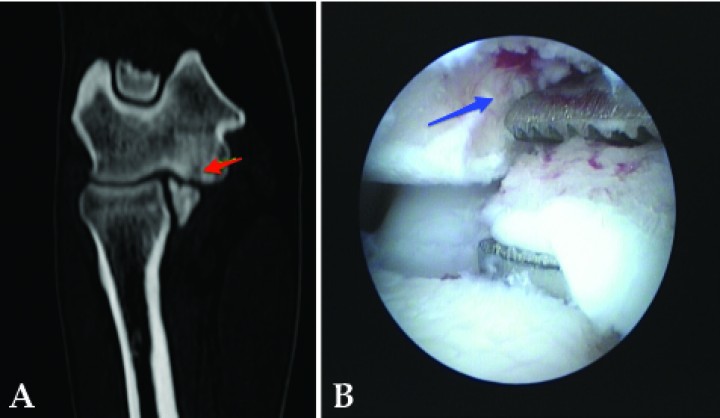

En cuanto al tipo de fragmentación coronoidea existe un amplio espectro de lesiones, desde condromalacias o fibrilaciones hasta verdaderas erosiones y úlceras, en ocasiones con microfisuras subcondrales. La fragmentación puede variar desde una simple fisura hasta fragmentos no desprendidos o fragmentos desprendidos unitarios o múltiples, entre otras (Fig. 8).

<p>Imágenes de tomografía computarizada en plano transversal y ventana de hueso. Se aprecian diferentes formas de fragmentación coronoidea. (<strong>A</strong>) Fragmentos mínimamente desplazados. (<strong>B</strong>) Multifragmentación con desplazamiento y deformidad de todo el ápex del proceso coronoides.</p>

Figura 8

Imágenes de tomografía computarizada en plano transversal y ventana de hueso. Se aprecian diferentes formas de fragmentación coronoidea. (A) Fragmentos mínimamente desplazados. (B) Multifragmentación con desplazamiento y deformidad de todo el ápex del proceso coronoides.